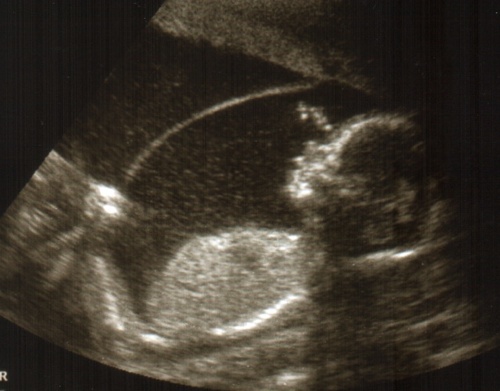

20 hetes UH képek

"A" baba

Kép

"B" baba

Megjöttem a genetikai UH-ról, minden rendben és nagyon úgy néz ki, hogy vegyespárosunk van:)

Szerintem még nem 100%-os, a kislányt én elég határozottan láttam, a kisfiút kevésbé, de azért valószínű:)